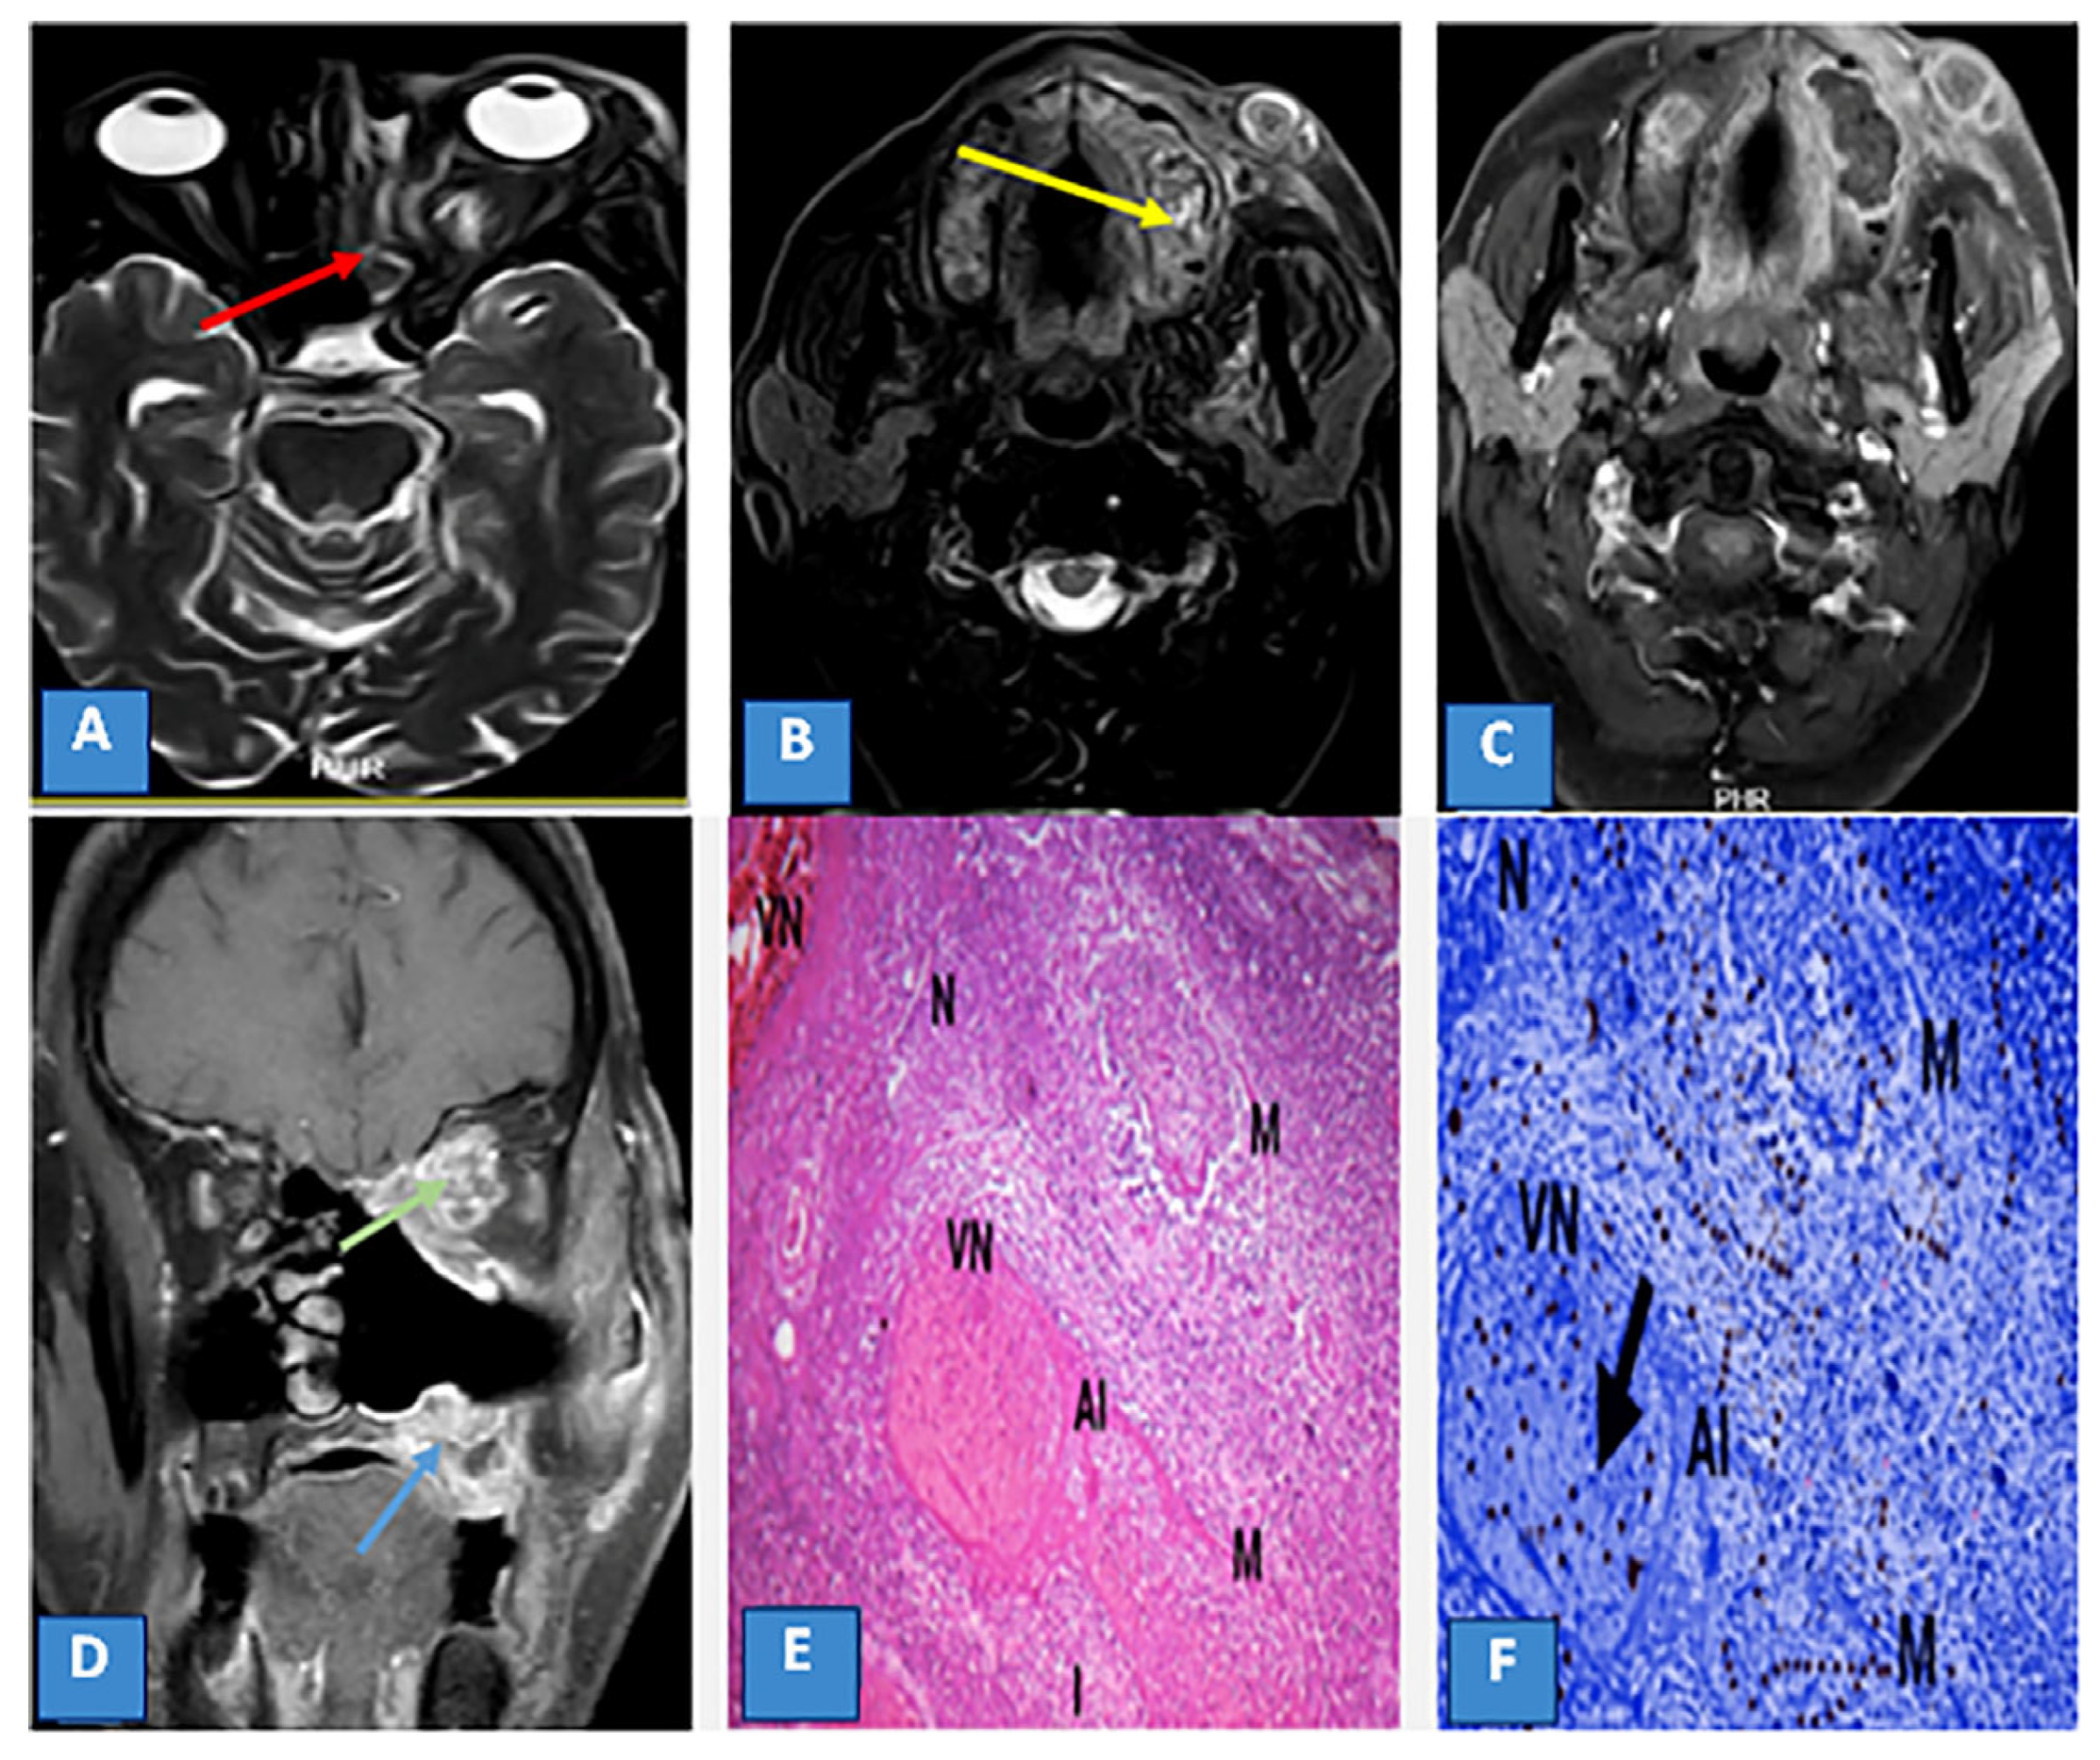

Magnetic Resonance Imaging Features of Rhino-Orbito-Cerebral Mucormycosis in Post-COVID-19 Patients: Radio-Pathological Correlation

3.3. MRI Findings and Signal Characteristics

3.4. Extrasinus Extension

3.5. Histopathological Findings